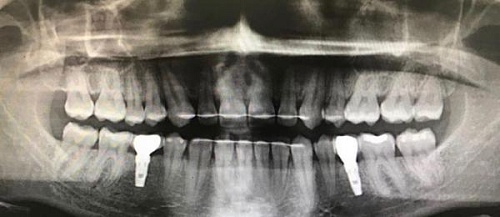

Сохранить зубы и пародонт помогает правильная гигиена полости рта дома и в кресле стоматолога, а также своевременное протезирование и имплантация, которые замещают удаленные зубы и равномерно распределяют жевательную нагрузку, не позволяя костной ткани атрофироваться.